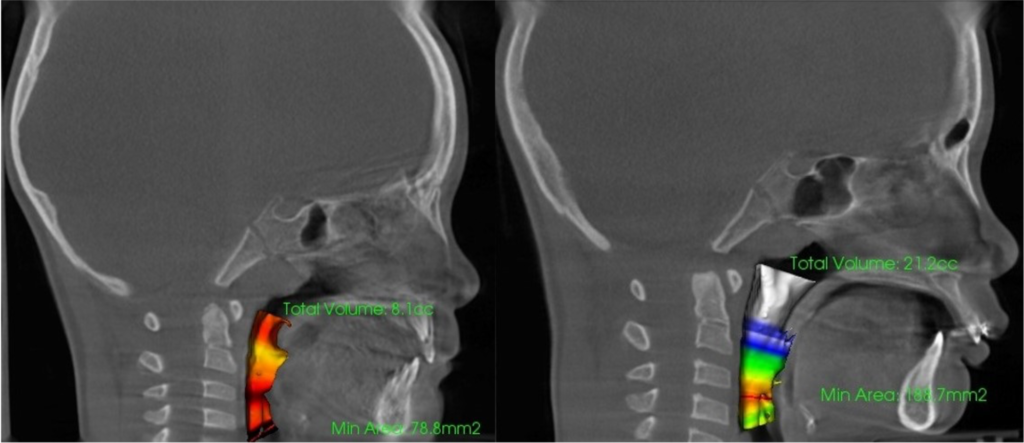

※気道容積・鼻副鼻腔容積の変化イメージ

- 鼻副鼻腔容積・気道容積計測=呼吸時の通気性

気道容積

鼻腔容積